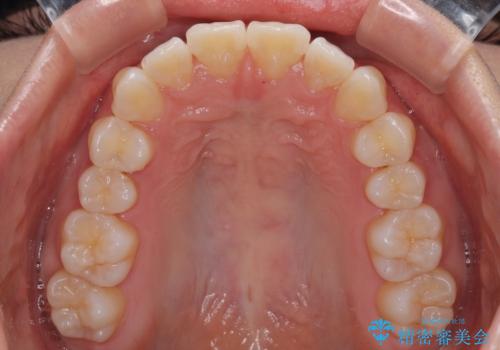

- 上の前歯の隙間を気にして来院された患者様です。

インビザラインにより、上下の歯列を側方に拡大しつつ、前歯の隙間を閉じていくこととしました。

隙間の原因は強い咬合力や舌の突出癖、小帯の異常付着などがありますが、舌のトレーニングをしっかりと行いながら、装着時間を遵守して装着していただいたおかげで、スムーズに治療を終えることができました。